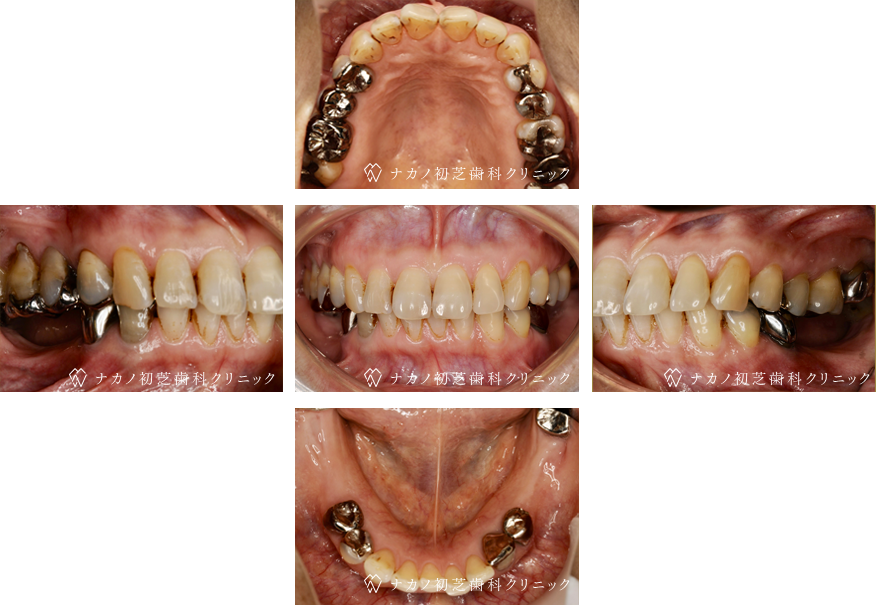

インプラント・7本 (60代男性)

-

BEFORE

AFTER

年齢 60代男性

治療内容 インプラント治療7本(骨造成の併用)

インプラント治療とは、歯を抜いた所にチタン製の人工歯根を埋入し、その上に歯を入れる方法です。骨を増やすことで、より審美的に治療が出来ました。費用 1本 400,000円(税込 440,000円)

リスク・副作用

腫れ・疼痛・違和感を感じるなどの症状を生じることがあります。